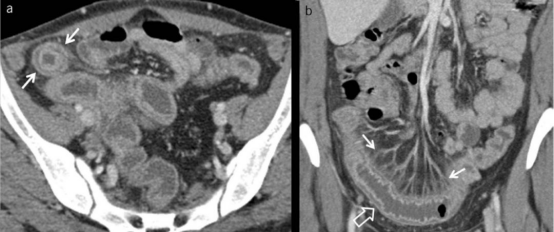

肠系膜血管炎:起病隐匿,多表现为间断发作的下腹痛,严重时出现恶心呕吐、腹泻、下消化道出血,甚至出现肠坏死、穿孔等急腹症,临床上常用的检查手段主要是腹部CT或核磁共振,主要表现为肠壁水肿增厚,呈“靶征”或“齿梳征”;